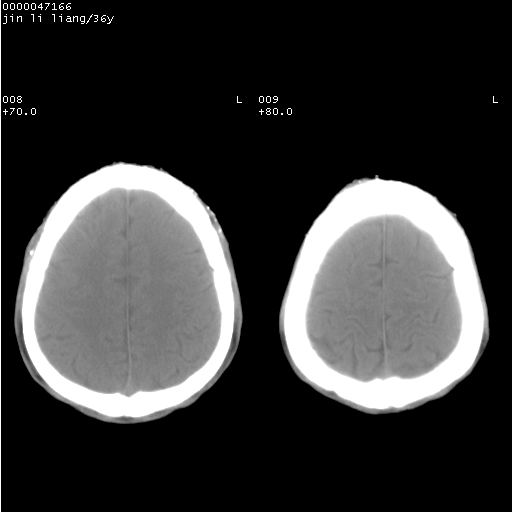

患者 男,36岁。头面部“土炮”炸伤。pe:面目全非,伤口流血不止。

临床诊断:头面部外伤。

颅脑ct轴位平扫(层厚、层距均为10mm),图像如下:

左眼球破裂并异物,眶周、额顶部头皮及软组织挫伤并异物

迎面一炮,满脸开曝。额顶部头皮及软组织挫伤并异物,左眼球破裂积气并异物,典型的面目全非,惨不忍睹。

左眼球破裂积气并异物,眶周、额顶部头皮及软组织挫伤并异物,右侧眼环前内分异物

1左侧眼球破裂并积气,球内、框内异物。

2额部顶部软组织伤。